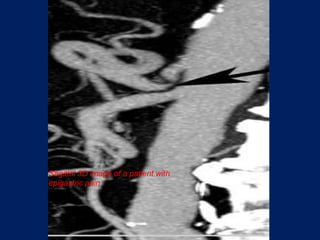

angulations and narrowing of the proximal celiac axis. Sagittal 3D image of a patient with epigastric pain

angulations and narrowingof the proximal celiac axis. Sagittal 3D image of a patient with epigastric pain

young patients (20–40 y), F : M  CT angiograms:            focal narrowing in the proximal celiac axis.             inspiration and expiration          2ry signs poststenotic dilatation and collaterals.ttt   : surgery.

young patients (20–40y), F : M  CT angiograms: focal narrowing in the proximal celiac axis. inspiration and expiration 2ry signs poststenotic dilatation and collaterals.ttt : surgery.